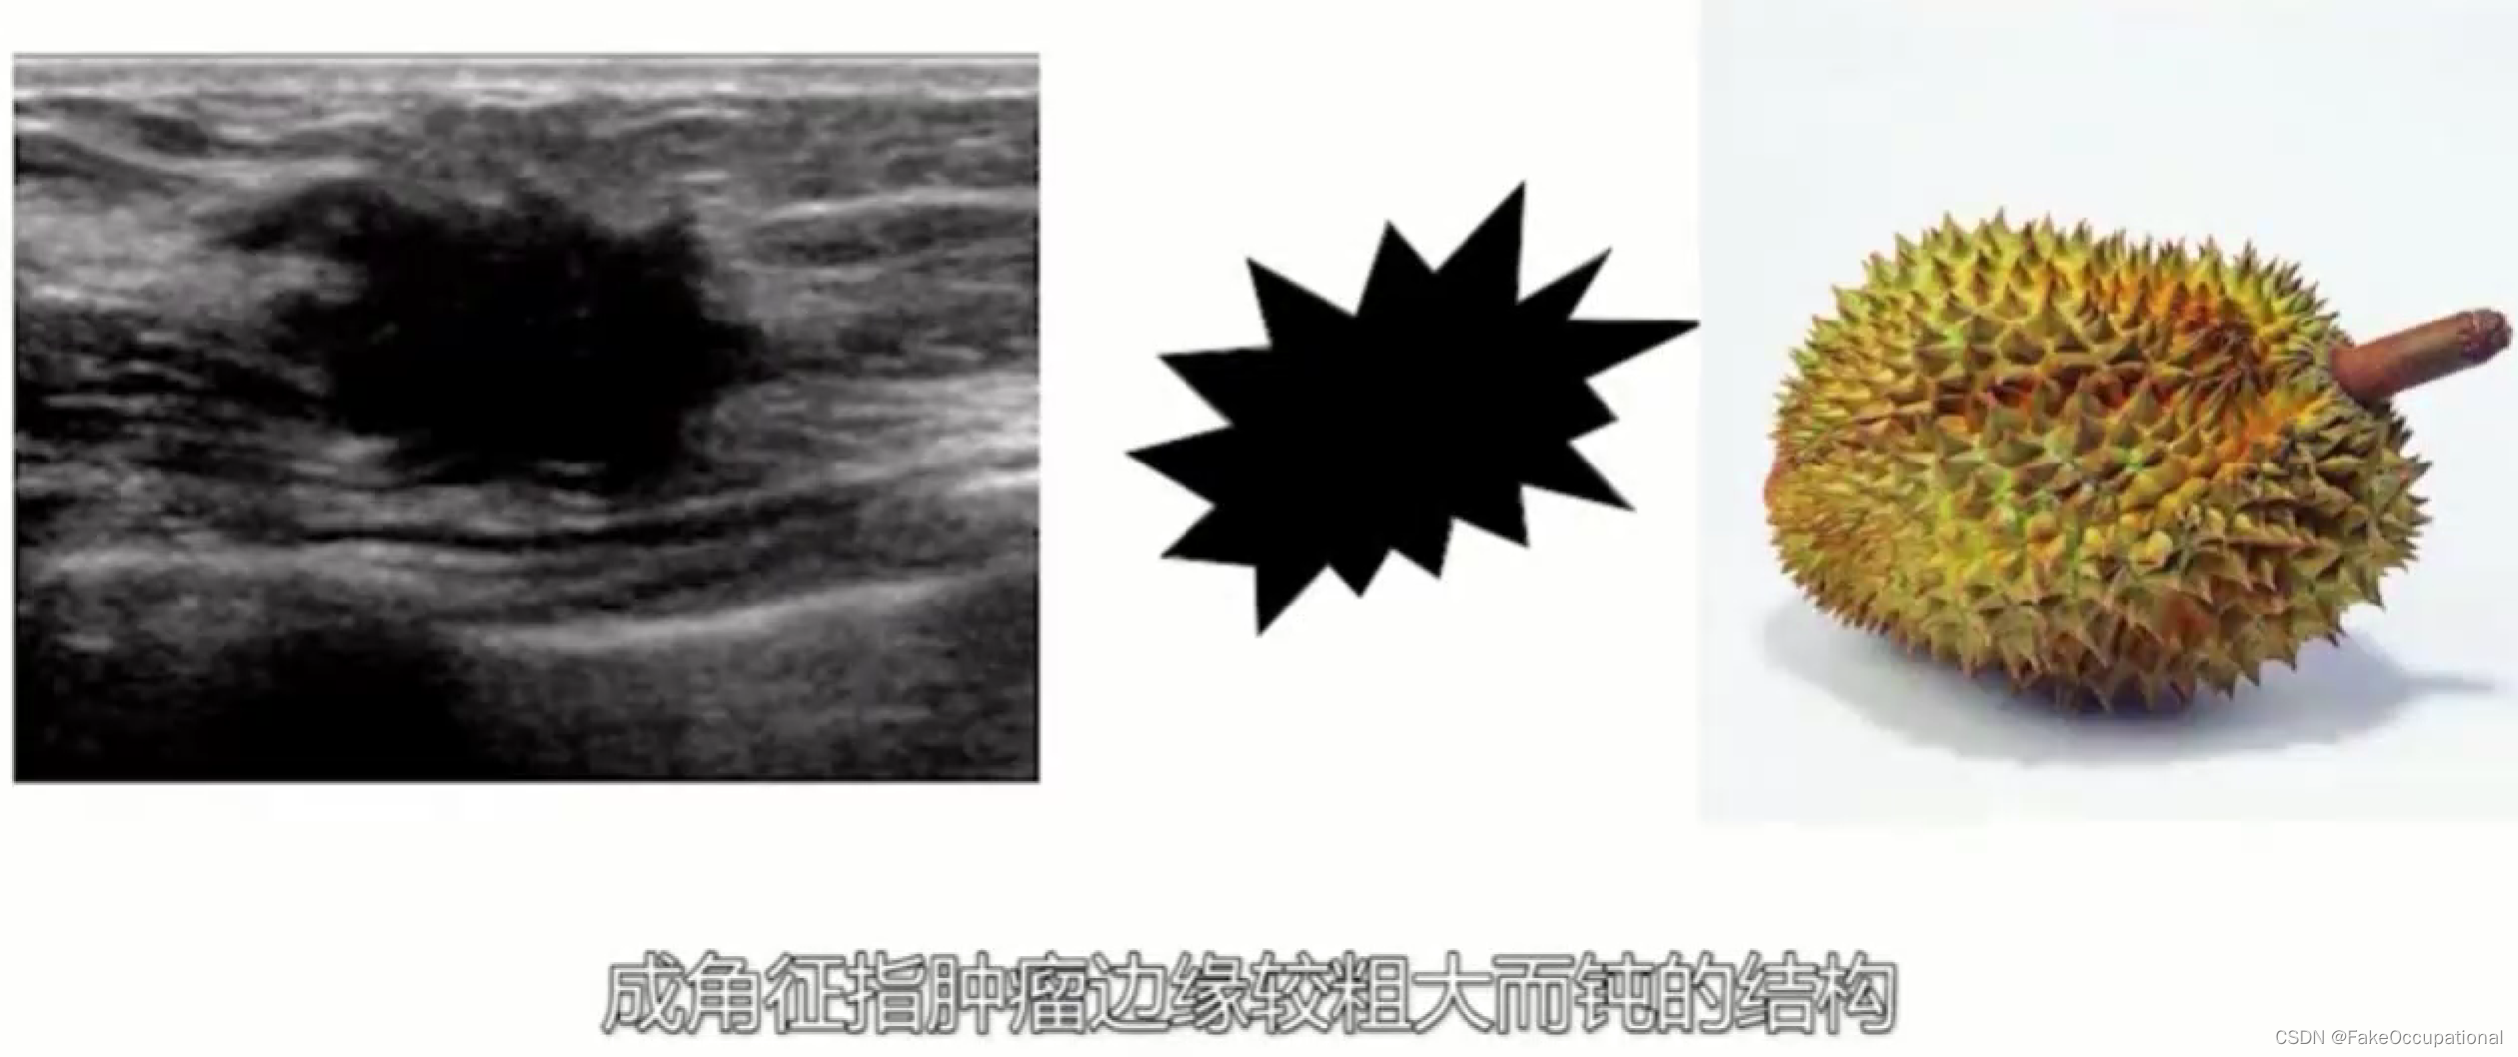

乳腺癌

- 患者18岁,微小癌

- 其理论依据是恶性肿瘤常星离心性生长